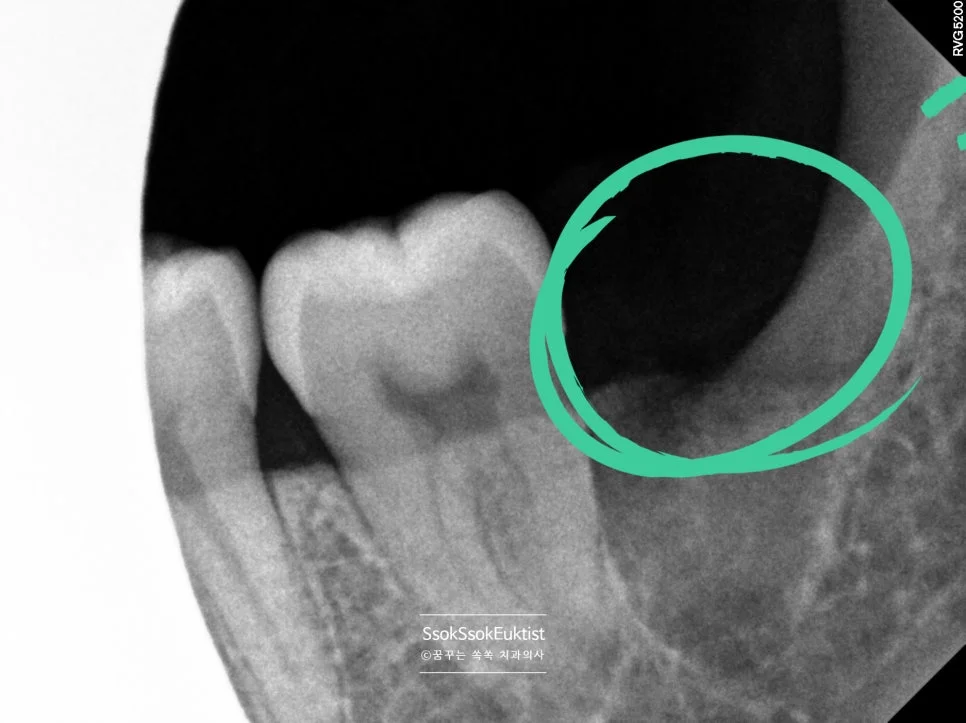

CBCT 좌측 하악 매복 사랑니 신경관 근접도 분석

좌측 CBCT — 신경관 근접도 분석

매복된 사랑니는, CT를 통해 신경관과 맞닿아 있진 않은지 정밀하게 분석 후 발치를 시도합니다.